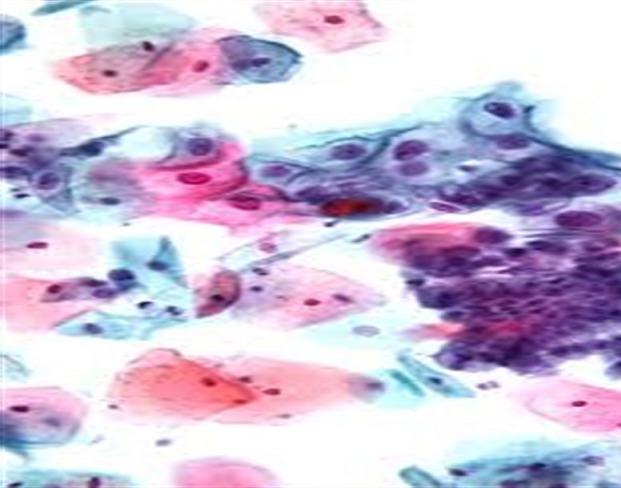

this is a descriptive analytical study carried out on eighty five (85) subjects aged between 23 and 68 years. Cervical samples were collected in liquid based medium and smears later examined after staining with Papanicolaou technique. These were categorized into low grade intra-epithelial lesion/malignancy, high grade intraepithelial lesion/malignancy according to the degree of dyskaryosis. Concentrations of interleukin 8 and interleukin 10 in the samples were determined by enzyme linked immunosorbent assay.

the mean age, standard deviation (SD) of the study subjects were 40.6 (7.8) years. A total number of 79 females (92.9%) were negative for intra-epithelial lesion/malignancy (NILM), while 4 (4.71%) and 2 (2.35%) were positive for low grade intra-epithelial lesion/malignancy (LILM) and high grade intra-epithelial lesion (HILM) respectively. While mean levels of interleukin 8 increased with the degree of malignancy, (107.27 ± 11.88pg/ml) in LILM, (114.80 ± 2.12pg/ml) in HILM when compared with NILM (88.39 ± 18.06pg/ml), (f = 0.700, p = 0.018); the mean levels of interleukin 10 was comparable between these groups (p ≥ 0.05). Pearson correlation coefficient analysis showed a negative association between interleukin 8 and interleukin 10 (r = -1.999, p = 0.000) in LILM.